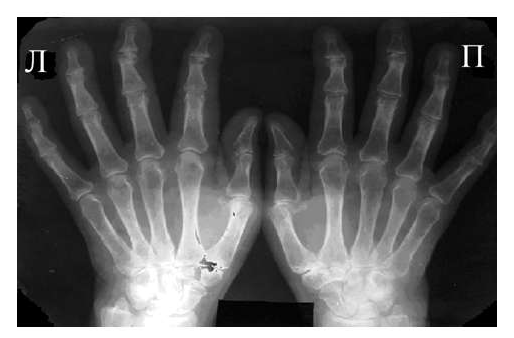

Поражение опорно-двигательного аппарата — одно из наиболее частных проявлений склеродермии. При рентгенологическом исследовании выявляются псевдоартриты, склеродермические полиартриты, остеолиз и кальциноз мягких тканей.

При псевдоартритах имеет место деформация суставов за счет фиброзно-склеротических изменений мягких тканей. На рентгенограммах выявляются сгибательные контрактуры и подвывихи в межфаланговых суставах, регионарный остеопороз. Однако деструктивные и литические изменения отсутствуют.

При склеродермическом полиартрите сочетаются фиброз периартикулярных тканей и эксудативные проявления. На рентгенограммах, уже на ранних стадиях, выявляются контрактуры и подвывихи. На фоне регионарного остеопороза могут выявляться одиночные краевые узуры с ободком склероза вокруг. Суставные щели сужены. Анкилозы наблюдаются редко.

При проведении дифференциальной диагностики с ревматоидным полиартритом следует учитывать, что при последнем рано выявляется диффузный остеопороз, в большей степени выражены деструктивные изменения. Характерно анкилозирование. Сгибательные контрактуры и подвывихи в межфаланговых суставах появляются достаточно поздно.

Явления остеолиза при склеродермии связаны с сосудисто-трофическими нарушениями. Лизис наиболее часто начинается с дистальных отделов ногтевых фаланг — когтевидных отростков (акроостеолиз). В дальнейшем остеолиз может распространяться на средние и даже основные фаланги, протекать с образованием секвестров или с полным рассасыванием костной ткани. По данным Н. Г. Гусевой (1975) акроостеолиз наблюдается у 41% больных склеродермией.

При склеродермии нередко приходится наблюдать кальциноз мягких тканей (синдром Тибьержа — Вейссенбаха, 1910). В мягких тканях пальцев рук и в периартикулярных тканях как мелких суставов кисти, так и крупных суставов верхних и нижних конечностей определяются отложения солей кальция или в виде точечных включений или в виде глыбок различной величины и формы.